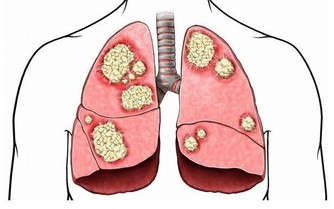

如果習慣晚上9點才吃晚飯,將會增加得乳腺癌和前列腺癌的風險。

一項研究發現,患有乳腺癌和前列腺癌患者更喜歡深夜進食。與晚上10點後相比,晚上9點前進食,男性患前列腺癌和女性患乳腺癌的風險平均降低18%。